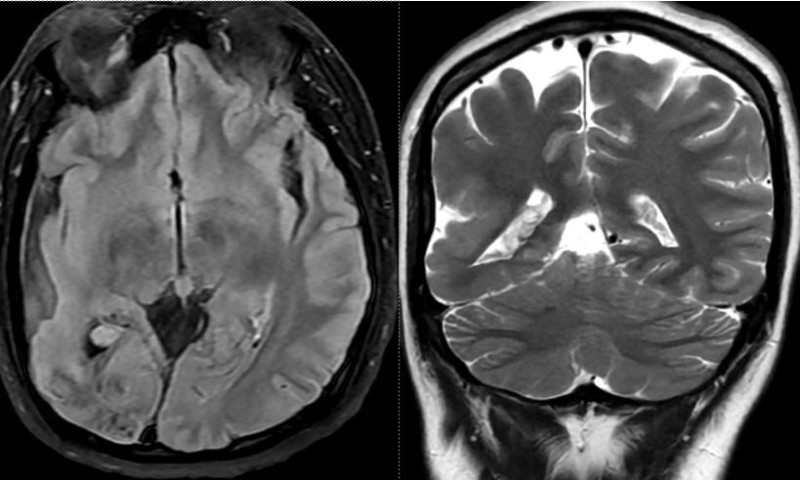

Kết quả chụp cộng hưởng từ (MRI) sọ não cho thấy nhiều bất thường đáng chú ý, bao gồm tổn thương cũ có vôi hóa, teo não thùy chẩm phải, khu vực liên quan trực tiếp đến đường dẫn truyền thị giác. Ngoài ra, hình ảnh còn ghi nhận phì đại đám rối mạch mạc trong não thất bên phải và thiểu sản động mạch đốt sống phải đoạn nội sọ.

Dựa trên các biểu hiện lâm sàng điển hình kết hợp với kết quả chẩn đoán hình ảnh, các bác sỹ xác định bệnh nhân mắc hội chứng Sturge-Weber. Sau khi chẩn đoán, bệnh nhân được tư vấn theo dõi lâu dài và xây dựng phác đồ điều trị nội khoa nhằm kiểm soát triệu chứng, hạn chế biến chứng.

Hiện nay, chẩn đoán hội chứng Sturge-Weber chủ yếu dựa vào thăm khám lâm sàng kết hợp các phương tiện chẩn đoán hình ảnh hiện đại như MRI, CT scanner, khám chuyên khoa mắt và điện não đồ. Do là rối loạn bẩm sinh, bệnh không có biện pháp phòng ngừa đặc hiệu, việc phát hiện sớm và điều trị kiểm soát triệu chứng đóng vai trò then chốt trong cải thiện chất lượng sống cho người bệnh.